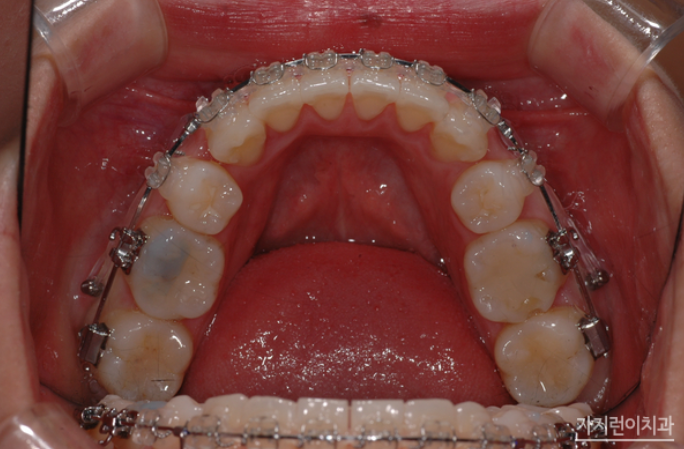

치아 재교정은 잇몸이나 치아 상태가 약해져 있는 상태에서 다시 시작하는 것이기 때문에, 교정을 전문으로 하는 치과를 선택하는 것이 중요한데요. 경험과 노하우가 있는 의료 인력이 있는 곳을 찾아 상태에 따른 정확한 상담과 치료 계획을 세우는 것이 필요합니다. 그래서 대부분은 치과가 많이 모여있는 밀집된 지역을 선호하시는데요. 이곳저곳 어슬렁 거리면서 나에게 맞는 교정치과를 찾기란 쉽지 않기 때문에 접근성이 편리한 치과 위주, 후기가 좋은 치과 위주로 알아보곤 하십니다.

무리한 재교정은, 비추 드리고 싶은데요. 현재 치아 상태와 잇몸 상태에 맞춰 완성도 높은 결과를 위해 높은 숙련도를 가지고 있는 치과교정과 전문의가 진료하는 곳인지, 첫 상담부터 사후 관리까지 꼼꼼하게 관리해 주는 곳인지 파악한 후 진행하는 게 좋습니다. 진단 후 가능한 범위내에서 안전하게 재교정해보는 게 좋겠죠?

재교정은 무리하게 진행하게 될 경우 치아가 약해져 교정을 안 하느니만 못하는 결과를 초래할 수 있으니 재교정이라는 불안감을 안고 있다면 의료진의 권고에 잘 협조해 용기를 내보는 게 좋겠습니다. 본원은 치아교정 전문치과로, 치아재교정을 포함해 사랑니를 세우는 치아교정, 직장인들이 선호하는 콤비교정, 돌출입교정, 옥니교정, 비발치교정, 비수술교정 등 다양한 교정을 진행하고 있는데요. 자연스럽게 입이 다물어지고, 이상적인 측면 페이스라인 등, 교합과 더불어 가지런한 치아배열을 만들어보고 싶다면 서울 가지런이치과 교정과 의원을 찾아 도움 받아보시기 바랍니다.